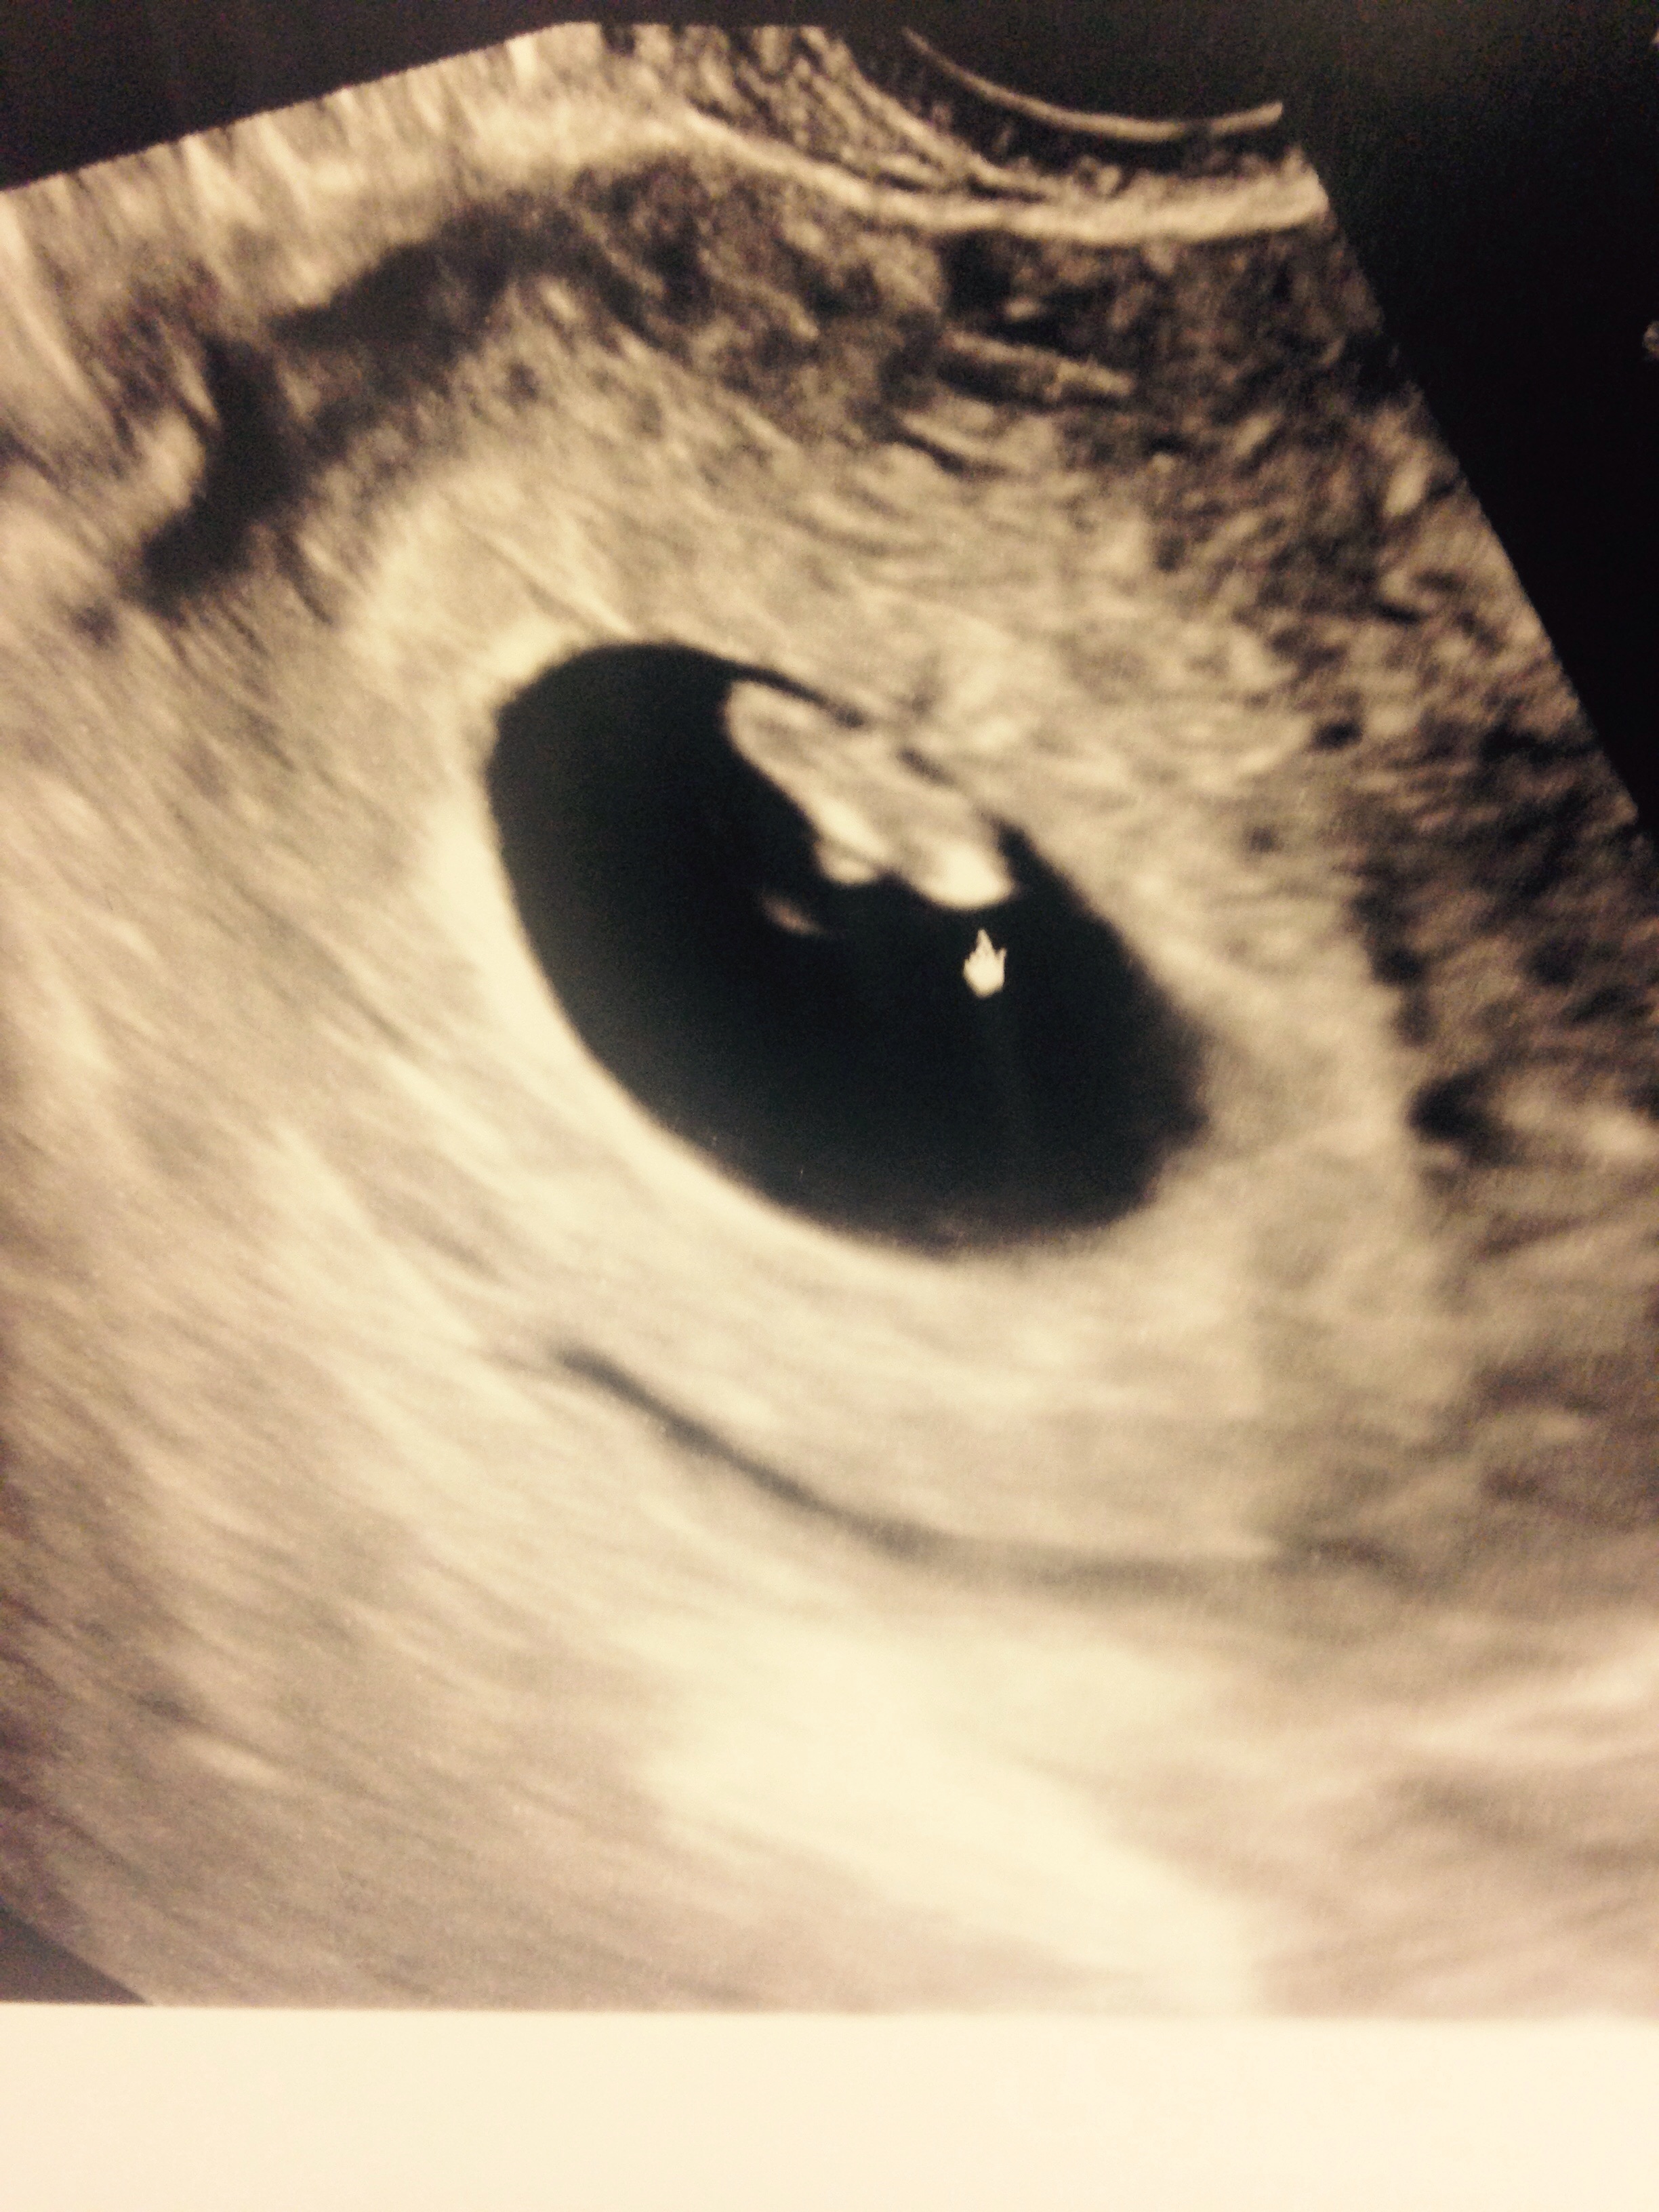

After a spotting episode and the baby measuring smaller, I went and got my official ultrasound and the baby is looking good! I'm 7 weeks 2 days due on July 28 and the heart rate was 148 bpm. I am so excited and I feel a lot less worried for now. Here's our sweet little bean